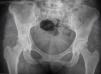

En la radiografía AP de pelvis encontramos CE de 42 y ángulo de Tonnis de 0 con signos de radioopacidades difusas múltiples en la región glútea compatibles con el antecedente de los biopolímeros (fig. 2).